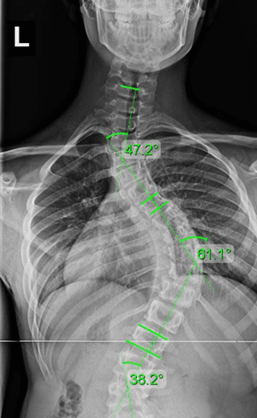

اسکولیوز شدید

اسکولیوز شدید به حالتی اطلاق میشود که انحنای ستون فقرات بیش از ۴۵ درجه است. در این وضعیت، انحنای ستون فقرات میتواند به شدت بر عملکرد بدن تأثیر بگذارد و مشکلاتی جدی مانند درد مزمن، فشار بر ریهها و قلب، و محدودیتهای حرکتی ایجاد کند. در این مرحله، درمانهای غیرجراحی معمولاً مؤثر نبوده و جراحی برای تصحیح انحنا و جلوگیری از مشکلات بیشتر، مانند آسیب به اندامهای داخلی، غالباً توصیه میشود.

شرایط شدید بودن اسکولیوز

- انحنای ستون فقرات بیشتر از ۴۵ درجه

- درد شدید و مزمن در ناحیه کمر یا گردن که ممکن است با فعالیتهای روزانه تداخل داشته باشد.

- مشکلات تنفسی یا قلبی به دلیل فشاری که بر اندامهای داخلی وارد میآید.

- محدودیتهای قابل توجه در حرکت و انجام فعالیتهای روزانه

- نیاز به جراحی برای تصحیح انحنای ستون فقرات و جلوگیری از عوارض جدیتر

برای اندازهگیری شدت اسکولیوز زاویه کاب (Cobb Angle) را محاسبه میکنند. در این روش دو خط از شروع و پایان انحراف با همان زاویه میکشند و سپس آن دو خط را بهوسیله دو خط قائم دیگر به یکدیگر وصل میکنند. زاویهای که میان خطوط جدید شکل میگیرد، نشاندهنده میزان شدت انحراف است. در موارد بسیار خفیف، به دلیل زاویه کم، حتی ممکن است که تغییرات ظاهری در کمر و ستون فقرات مشاهده نشود، اما در موارد شدید علائمی مانند عدم تقارن شانهها یا لگن و همچنین برجستگی کتف در یک سمت مشاهده میشود.

- تصویربرداری

پس از اینکه اسکولیوز تشخیص داده شد، پزشک برای اندازهگیری دقیق میزان انحراف ستون فقرات درخواست تصویربرداری میکند. تصاویر رادیوگرافی به وضوح انحراف ستون فقرات را نمایش میدهد. پزشک از این طریق میتواند بررسی کند که ستون فقرات چقدر منحرف شده است. این تصویر معمولاً از دو جهت گرفته میشود: یکی از جلو (پروب به جلو) و دیگری از کنار (پروب به پهلو) تا انحراف در هر دو بعد مورد بررسی قرار گیرد.

- بررسی میزان انحراف

پس از گرفتن تصویر، پزشک میزان انحراف ستون فقرات را با دقت اندازهگیری میکند. این اندازهگیریها معمولاً با استفاده از خطوط مرجع انجام میشود که پزشک روی عکس رادیوگرافی رسم میکند. این خطوط به طور خاص در نقاطی از ستون فقرات که انحراف وجود دارد، کشیده میشوند. پزشک این خطوط را بررسی میکند تا زاویهای که انحراف ایجاد کرده را اندازهگیری کرده و میزان شدت انحراف را تعیین کند.